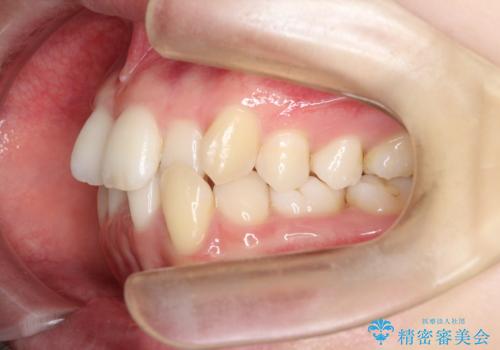

- 患者様は、前歯のガタガタ(叢生)と左下5番の欠損部が気になるとのことで来院されました。診断の結果、インビザラインを用いて前歯の叢生を整えながら、左下5番の欠損部にはインプラント治療を計画しました。矯正治療により、歯並びを改善すると同時に、噛み合わせのバランスも向上させることを目標としました。矯正期間とインプラントの治療計画を並行して進めることで、患者様のご希望に応えるプランを立てました。

前歯の叢生改善のため、インビザラインによる透明で目立たない矯正装置を使用しました。治療中は、歯の移動による負担を最小限に抑えつつ、歯列全体のバランスを考慮して進めました。左下5番の欠損部には、矯正終了後にインプラントを埋入し、自然で機能的な咬合を回復しました。治療期間中、患者様には装置の正しい装着と日々の清掃を徹底していただき、歯肉やインプラント周囲の健康を保つようサポートしました。結果として、美しい歯並びと快適な噛み合わせを両立させることができました。